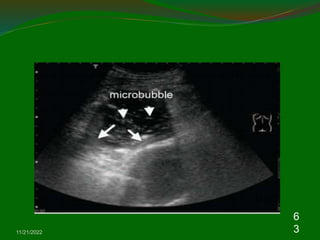

5. Pneumothorax

Chest US may be help in the diagnosis of

pneumothoraces.

Normal parietal and visceral pleura slide over each other

during respiration and a pneumothorax is suspected

when this ‘Gliding sign’ is absent in chest US

A recently published systemic review, chest US had a

sensitivity of 90.0% and a specificity of 98.2% .

The confirmation of lung gliding has a 100% negative

predictive value for the absence of pneumothorax .

The use of M-mode can also objectify the presence or

absence of lung gliding